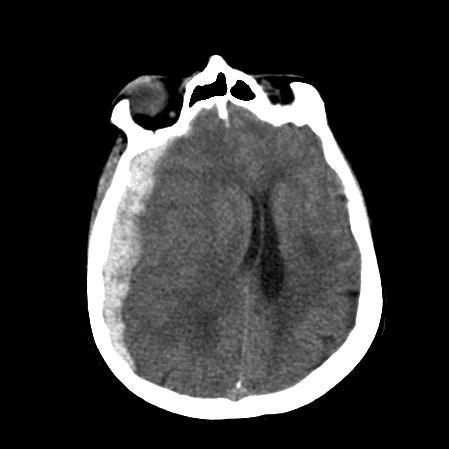

Subarachnoid Haem